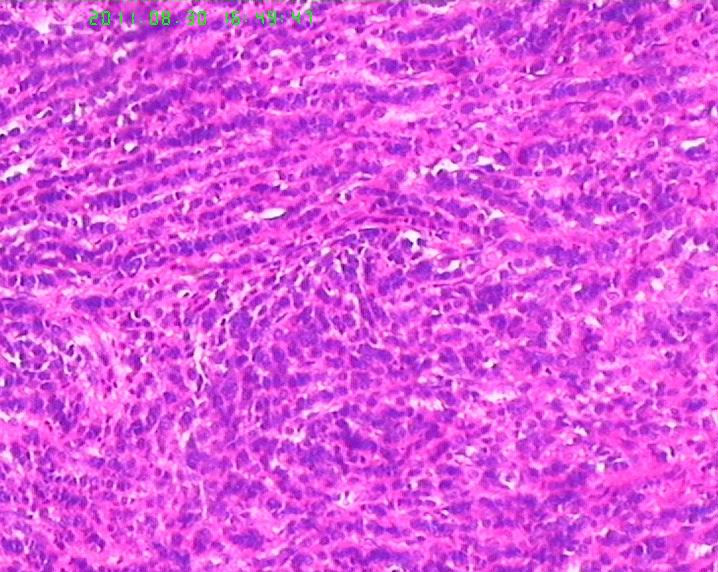

此例男,65岁。术前胃镜活检学生报告“低分化腺癌”,行手术治疗。术后见胃体后壁小弯测溃疡性肿物直径6.5cm,周围隆起质地硬,肉眼侵及肌层。镜下所见如图,似乎不是腺癌,是否是类癌??但核分裂很活跃,不见核仁。胃周淋巴结未检出转移。请老师们帮忙指正。学生感激。

肿瘤呈流水线样排列,有腺样结构,核分裂像多见,从这些来说至少不是类癌了,如果是神经内分泌肿瘤,那也应该是神经内分泌癌了,此例可能为腺癌伴神经内分泌分化,需做免疫标记证实是否有神经内分泌分化。

应加做神经内分泌标记物Syn、CgA、CD56和Ki67,小细胞癌/未分化癌不能排除。

本例需要除外神经内分泌癌的可能(比类癌恶性程度高,本例应达到是NET 3级)。

若诊断管状腺癌,其中未见任何“管腺”形成迹象,故应诊断为“未分化腺癌”。但学生有以下疑问:1、为何肿瘤与正常胃粘膜交界处不见“非典型增生腺体”移行,而是截然交界。交界处可见淋巴细胞浸润。2、为何肿瘤浸润肌层的界面圆顿,如同“疣状癌”的膨胀性推挤生长。3、未分化腺癌恶性程度高,而为何胃周淋巴结检出二十余枚均未见转移。

细胞排列器官样,细胞核染色质较细腻,第一考虑类癌,第二除外低分化腺癌.加染IHC最后定类型.